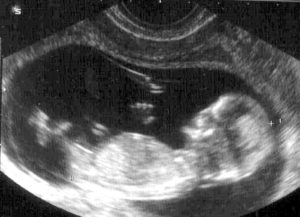

На 12 и 13 неделе беременности УЗИ уже может показать пол малыша. Эта новость ни может не будоражить будущую маму!

Скрининг. УЗИ 12 недель беременности — плановое исследование, которое проводится в конце 1 триместра.

Вместе с УЗИ женщина сдает кровь на биохимический анализ, чтобы исключить риски неправильного развития плода, тонус матки и генетические заболевания. Такие исследования не опасны для малыша, если делать их в установленные даты.

Зато они очень информативны, поэтому игнорировать их не стоит. Приятный бонус исследования — ты узнаешь пол своего малыша.